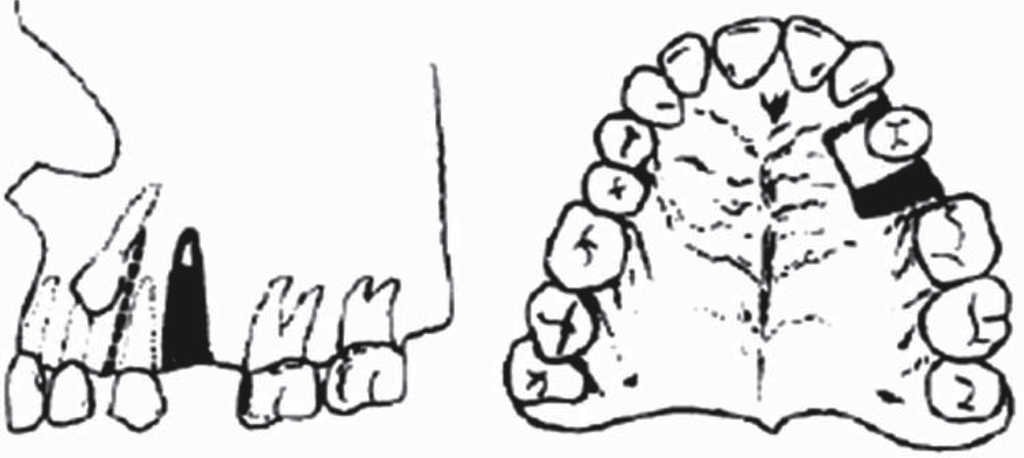

Bone block technique (Köle 1959)

In 1959 Heinrich Köle introduced the description of a corticotomy technique associated to orthodontic treatment to accelerate dental movement under the theory of bone block movements.5 He proposed that tooth movement could be achieved in shorter time if interdental and osteotomies cuts were performed, since cortical bone represented greater resistance to tooth movement, and thus, if cortical bone continuity was altered, tooth movements could be achieved in shorter time.5

This surgical technique consisted on raising a muco-periosteal flap (from a vestibular and lingual/ palatal direction), and conduct osteotomies in inter-radicular and supra-apical sites. Cuts should measure 10 mm and be located above all apexes; a perpendicular (horizontal) cut should be undertaken, achieving thus separation of small-sized bone blocks to provide acceleration of orthodontic movement (Figure 1).4 It is important to point out that most movements described by Köle were movements conducted with orthopedic forces applied through removable devices adapted by adjustable screws. Since this technique was highly invasive it garnered little acceptation.2 4

The advantage of this technique was that it provided faster tooth movement in shorter time (approximately 6 to 12 weeks). This procedure was recommended for separation of single or grouped teeth, it was used to achieve distally-oriented movements after an extraction (Figure 2).4